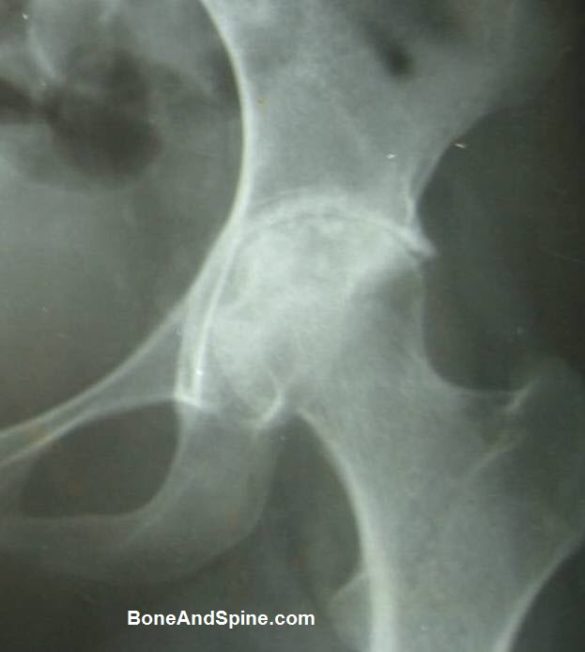

Tuberculosis of the hip — radiographic findings

X-rays can be normal initially but can show joint space narrowing, decreased bone density, and very little reactive bone formation. MRI shows bone and joint involvement well. Current standard requires biopsy of the involved tissue to confirm the diagnosis. Cultures of mycobacteria take a long time, but genetic tests of the biopsy specimen give quick results.